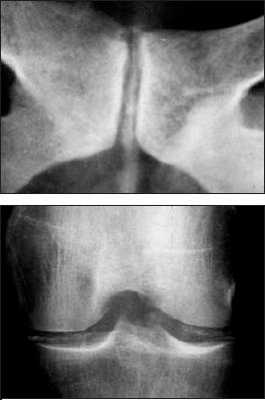

Болезнь отложения кристаллов кальция пирофосфата дигидрата (БКПД) в медицинской литературе известна под тремя названиями: «псевдоподагра», «хондрокальциноз» и «пирофосфатная артропатия». Однако приведенные определения явно не удовлетворяют современным требованиям к номенклатуре заболеваний, стремящимся к максимально полной характеристике патологического процесса. Так, термин «псевдоподагра» точно описывает клинические проявления бурного синовиального воспаления при БКПД, схожего с атакой подагрического артрита, но подобные приступы наблюдаются далеко не у всех пациентов. Термин «хондрокальциноз» описывает рентгенологическую картину отложения кристаллов пирофосфата кальция в гиалиновом хряще и других внутрисуставных структурах (менисках), наблюдаемую у пациентов с БКПД. Однако данные рентгенологические признаки (кальцификация мягких тканей) могут наблюдаться и при других состояниях. Наконец, наиболее часто встречающийся термин «пирофосфатная артропатия» свидетельствует о существующем в течение длительного времени определенном агностицизме в представлениях врачей о данном заболевании. Распространенность . БКПД – это болезнь пожилых людей, со средним возрастом пациентов 70 лет. В этом возрасте отложения пирофосфата кальция в гиалиновом хряще являются нередкой находкой. Эпидемиологические исследования (включавшие рентгенологическое обследование коленных суставов, суставов кистей и таза) свидетельствуют о прямой связи распространенности суставного хондрокальциноза с возрастом: в 65–74 года хондрокальциноз обнаруживают у 15%, в 75–84 года – у 36%, в возрасте более 84 лет – почти у 50% обследуемых независимо от присутствия симптомов. Данные по более молодым возрастным группам отсутствуют. Причины отложения кристаллов пирофосфата кальция при старении хряща остаются неясными. Отчетливых половых различий в частоте БКПД не найдено, однако вариант «псевдоподагры» наблюдается чаще у мужчин, а «псевдоостеоартроза» – у женщин. Отложение кристаллов кальция пирофосфата дигидрата представлено на рентгенограммах. Патогенез . Основным патогенетическим механизмомБКПД является образование и накопление кристаллов пирофосфата кальция . Пирофосфат (дифосфат) кальция диг и д р а т , Са2(Р2О7)2Н2О, представляет собой естественную неорганическую соль кальция, присутствующую в тканях организма. Патогенез БКПД кардинальным образом отличается от патогенеза подагры – другого распространенного заболевания из группы микрокристаллических артритов. Если при подагре образование кристаллов уратов происходит в синовиальной жидкости или во внесуставных тканях (формирование тофусов) на фоне общего повышения уровня мочевой кислоты в тканевой жидкости, то при БКПД первичной зоной кристаллообразования является толща гиалинового или волокнистого хряща при нормальном уровне кальция в других тканях организма. В норме этот процесс наблюдается при физиологической минерализации хрящевой пластинки в период роста кости, но нормальный гиалиновый хрящ не кальцифицируется. В течение последнего времени получены определенные данные, проясняющие патогенез БКПД. Установлено, что образование кристаллов пирофосфата начинается в зоне хряща, прилегающей непосредственно к мембране хондроцитов. Образование и накопление кристаллов пирофосфата могут быть результатом как повышенного локального уровня кальция, так и изменений в перицеллюлярном матриксе (протеогликанах и коллагене), приводящих к перенасыщенности присутствующего здесь пирофосфата кальция или комбинацией этих факторов. Современные достижения в молекулярной патологии и гистохимии определили потенциальные факторы, участвующие в этом процессе. Типичными морфологическими признаками, предшествующими минерализации хряща в ростовой пластинке кости, являются гипертрофия хондроцитов и их усиленный апоптоз . Эти же признаки наблюдаются в хряще при остеоартрозе (ОА) и описаны, как самые ранние морфологические признаки БКПД. Механизм связи между интенсивной продукцией протеогликанов гипертрофированными хондроцитами и образованием кристаллов при БКПД неясен. Однако электронно–микроскопические и иммунохимические исследования показали, что в гипертрофированных хондроцитах при БКПД присутствуют измененные протеогликаны, меньшего размера в сравнении с нормой, и дегенеративно измененные короткие цепиколлагена. При гипертрофии хондроцитов имеет место избыточная продукция коллагена X типа, матриксной металлопротеиназы–13 и щелочной фосфатазы, которые также влияют на процесс кальцификации. Показано, что гипертрофия хондроцитов сопровождается изменениями в продукции трансглютаминазы, фермента – представленного двумя типами: трансглютаминазой–2 (ТГ2) и фактором XIIIА. Функция трансглютаминаз заключается в посттрансляционном образовании поперечных связей в белках, происходящем как внутриклеточно, так и во внеклеточном матриксе. Наличие поперечных связей в кальций–связывающих белках постулируется как условие стабилизации матрикса и минерализации хряща ростовой пластинки. Трансглютаминазы могут модулировать кальцификацию хряща непрямым образом посредством активации мощного кристаллообразующего фактора – ростового фактора– ? . На животных моделях показано, что хондроциты гиалинового хряща экспрессируют ТГ2 и фактор XIIIА и что их активность усиливается с возрастом. ТГ2 ответственна за увеличение концентрации неорганического пирофосфата в экстрацеллюлярном пространстве хондроцитов и является основным регулятором процесса кальцификации хряща. Эти данные были подтверждены гистохимическими исследованиями на тканях человеческого мениска и суставного хряща при ОА; нарушения регуляции ТГ2 и фактора XIIIА были обнаружены как в поверхностной и глубокой зонах хряща при ОА, так и в центральной зоне дегенеративного мениска. Определенным образом в патогенезе БКПД играют роль генетические факторы. Известна семейная форма БКПД, при которой хондрокальциноз регистрируется у членов одной семьи в более молодом возрасте, чем в среднем в популяции. Существует линия мышей ( «tiptoe–walking» mouse ), характеризующаяся точечной мутацией, приводящей к дефициту фермента фосфодиэстеразы; при этом наблюдается избыточная минерализация осевого скелета. Состояния, ассоциированные с хондрокальцинозом В отличие от истинной БКПД существуют состояния, при которых отложение кристаллов пирофосфата кальция в хряще лишь сопровождает основной патологический процесс. К ним относятся травматические поражения суставов, ряд метаболических и эндокринных заболеваний, которые необходимо исключать при постановке диагноза БКПД, особенно при начале клинических проявлений в молодом возрасте. В частности, при обнаружении хондрокальциноза в отдельных суставах у молодых людей необходим тщательный сбор анамнеза, в ряде случаев позволяющий связать этот признак с предшествующей травмой сустава или хирургическим вмешательством на нем. Патогенез посттравматического кальциноза мягкотканых структур суставов (менисков в коленных и треугольного хряща в лучезапястных) идентичен наблюдаемому при естественной инволюции гиалиного хряща. Хондрокальциноз встречается при гемохроматозе – относительно редком заболевании, спектр признаков поражения опорно–двигательного аппарата при котором близок клиническим проявлениям БКПД (псевдоподагра, хондрокальциноз, хроническая артропатия). Влияние накопления железа в тканях организма на патологическую минерализацию также подтверждается обнаружением отложений кристаллов пирофосфата в суставах при гемосидерозе и гемофилической артропатии. Другие состояния и предрасполагающие факторы . Помимо гемохроматоза, известен ряд других метаболических и эндокринных заболеваний, ассоциированных с отложением кристаллов пирофосфата кальция. Обнаружение рентгенологических и клинических признаков БКПД всегда требует исключения этих состояний, особенно у молодых пациентов (табл. 1). Описаны случаи развития острого суставного воспаления, связанного с кристаллами пирофосфата, после внутрисуставного введения гиалуроната и внутривенного введения памидроната. Возможной причиной может быть нарушение равновесия между концентрациями фосфата кальция в синовиальной жидкости и окружающих тканях, приводящее к выбросу (или образованию) кристаллов в полость сустава. Клиника БКПД представлена несколькими клиническими вариантами. Наиболее часто встречается «псевдоостеоартроз» , характеризующийся умеренными болями (преимущественно механического ритма) в пораженных суставах (наиболее часто – коленных), ограничением подвижности. Также как при ОА, дегенеративный процесс может сопровождаться формированием остеофитов (узелки Бушара и Гебердена) и варусной деформацией коленных суставов (в ряде случаев вызванной асептическим некрозом медиальных мыщелков). Рентгенологические признаки хондрокальциноза обнаруживаются во многих суставах, однако клиническая значимость определяется поражением отдельных суставов, чаще всего коленных. Симптомы воспаления присутствуют (как и при идиопатическом ОА), но носят умеренный характер и не отражаются на лабораторных показателях. Признаками, позволяющими провести дифференциальный диагноз в пользу псевдоостеоартрозного варианта БКПД, являются необычная для ОА локализация пораженных суставов (лучезапястные, локтевые, плечевые, пястно–фаланговые, голеностопные суставы) и рентгенологически выявляемый в пораженных суставах хондрокальциноз. Сложным и в ряде случаев неразрешимым вопросом является интерпретация рентгенологических признаков БКПД (хондрокальциноза), определяемых у пациентов с типичной для ОА локализацией пораженых суставов – коленных, межфаланговых суставов кистей, у которых клинические проявления ОА появились раньше, чем рентгенологически регистрируемый хондрокальциноз. Сравнение данных рентгенологического исследования пораженных суставов за несколько лет и фиксирование лишь последующего появления хондрокальциноза на каком–то этапе дегенеративного процесса позволяют сделать вывод о вторичности отложения пирофосфата кальция в пораженном хряще. «Псевдоревматоидная» форма БКПД наблюдается у 5% пациентов и характеризуется симметричным поражением пястно–фаланговых суставов, обычно II–III пальцев, протекающим с утренней скованностью, иногда с формированием сгибательных контрактур и умеренным повышением острофазовых показателей. Однако в отличие от истинного ревматоидного артрита наблюдается лишь умеренное воспаление, отсутствие эрозий суставных поверхностей и хондрокальциноз. «Псевдоподагрический» вариант представляет собой наиболее известное и яркое проявление БКПД. Бурное микрокристаллическое воспаление возникает в ответ на высвобождение значительного количества кристаллов кальция пирофосфата из толщи хряща в синовиальную полость. Выраженность воспаления и его кратковременность (несколько дней, редко более недели) определили название этого варианта БКПД. Данный вариант БКПД традиционно фигурирует в перечне причин острого моноартрита (две другие – подагра и инфекционный артрит). В отличие от истинной подагры первый приступ возникает в возрасте 50 лет и старше (исключение – семейная наследственная форма БКПД), воспаление практически всегда локализовано в коленных суставах, реже в других и крайне редко – в I плюснефаланговом суставе. Женщины страдают этой формой БКПД почти с такой же частотой, как и мужчины. Как и при истинной подагре, провоцирующими факторами могут быть травма, хирургическое вмешательство, нарушение мозгового кровообращения и инфаркт миокарда. Отмечена сезонность – приступы достоверночаще возникают весной. До и между приступами острого воспаления сустав, как правило, асимптоматичен. Однако возможно развитие приступа острого воспаления отдельных суставов и у пациентов с «псевдоостеоартрозной» формой БКПД. Наиболее редко (описаны единичные случаи) БКПД проявляется псевдонейропатической артропатией , обычно коленных суставов, при которой формируется клиническая и рентгенологическая картина артропатии Шарко. В отличие от истинного сустава Шарко (встречающегося при tabes dorsalis и сирингомиелии) эта форма БКПД не сопровождается признаками поражения центральной и периферической нервной системы. Асимптомный хондрокальциноз , как уже указывалось, нередко обнаруживается у пожилых людей. У пациентов с клиническими признаками БКПД в отдельных суставах хондрокальциноз может быть выявлен и в других, клинически интактных, суставах. Считать ли асимптомный хондрокальциноз болезнью? По–видимому, здесь справедлива та же позиция, которая в настоящее время существует в отношении рентгенологических проявлений и диагноза остеоартроза – «нет симптомов – нет болезни». Подобная аналогия представляется уместной, так как и рентгенологические проявления остеоартроза (остеофиты, сужение суставной щели) и хондрокальциноз имеют отчетливую корреляцию с возрастом и могут представлять собой варианты естественной инволюции опорно–двигательного аппарата, не сопровождающиеся клиническими симптомами. Известно, что выраженность клинических проявлений БКПД не связана с выраженностью хондрокальциноза. Лечение В связи с неясностью до настоящего времени точного механизма, приводящего к формированию и накапливанию кристаллов пирофосфата кальция в гиалиновом хряще, патогенетических методов лечения этого заболевания не существует. При псевдоостеоартрозе применяется тот же комплекс лечебных мероприятий, что и при идиопатическом ОА, включающий разгрузку пораженных суставов, укрепление мыш, стабилизирующих пораженный сустав, симптоматический прием нестероидных противовоспалительных препаратов с учетом переносимости сопутствующей патологии. Принимая во внимание, что патогенез БКПД имеет общие детали с ОА (продукция хондроцитами дефектных протеогликанов), теоретически при БКПД можно ожидать эффект от приема структурно–модифицирующих препаратов, применяемых при ОА (глюкозамин, хондроитин, гиалуроновая кислота). Однако на сегодняшний день результаты подобных исследований не публиковались. Тактика при развитии острого воспаления, определяющего клинику псевдоподагры заключается, прежде всего, в исключении инфекционного артрита . Методом, позволяющим это сделать, является исследование синовиальной жидкости, включающее бактериологическое (окраска по Граму и посев) исследование и поиск в жидкости кристаллов. Визуальная характеристика синовиальной жидкости и обычное цитологическое исследование не позволяют провести дифференциальный диагноз между этими заболеваниями – высокий цитоз (вплоть до пиоидности) и преобладание нейтрофилов характерны как для БКПД, так и для инфекционного воспаления. При определенном опыте исследователя кристаллы пирофосфата кальция могут быть идентифицированы при обычной световой микроскопии (в отличие от игловидных уратов они имеют вид параллелепипедов с «обрубленными» концами, ромбов). Более достоверным способом обнаружения и идентификации кристаллов является микроскопия в поляризованном свете с применением компенсатора , при которой определяется способность кристаллов пирофосфата к слабому двойному лучепреломлению (рис. 1). Исследование в поляризованном свете позволяет обнаружить кристаллы пирофосфата кальция в 5 раз чаще, чем при обычной микроскопии. Диагноз значительно упрощается при развитии повторных приступов. Собственно, лечение приступа псевдоподагры не отличается от такового при остром приступе подагры. Эффективны традиционные НПВП, применяемые в средних и максимальных дозах. Среди современных комбинированных противовоспалительных средств, эффективных при остром приступе псевдоподагры, хорошо себя зарекомендовал Амбене – препарат, сочетающий мощную противовоспалительную активность глюкокортикостероида (дексаметазона) и НПВП (фенилбутазона), позволяющих быстро купировать приступ. Амбене выпускается в двух лекарственных формах (готовые шприцы и двойные ампулы) и назначается однократно в сутки, коротким курсом 3 инъекции в неделю ежедневно или через день. При затяжном приступе (длящемся более 3 дней, несмотря на энергичную противовоспалительную терапию) или при противопоказаниях к использованию НПВП методом выбора является введение в сустав адекватной дозы микрокристаллического глюкокортикостероида пролонгированного действия – триамцинолона ацетонида или бетаметазона дипропионата. Как правило, данная процедура проводится однократно, крайне редко возникает необходимость в повторном введении. Применение колхицина, как противорецидивного препарата при псевдоподагре, не получило распространения в связи с плохой переносимостью и отсутствием данных о его эффективности. Не подтвердилась эффективность солей магния, попытки введения которых в сустав при приступе псевдоподагры предпринимались с целью перевода кристаллов пирофосфата кальция в растворимое состояние. Таким образом, БКПД представляет собой известную, но до настоящего времени во многом загадочную нозологическую форму. Встреча с пациентом с предположительным диагнозом БКПД требует от врача как умения взвешенно подходить к интерпретации выявляемых инструментально признаков патологии (хондрокальциноза, обнаружения кристаллов пирофосфата кальция в синовиальной жидкости), так и (при подтверждении диагноза) определять тактику лечения для каждого пациента исходя из принципов достаточности и безопасности.